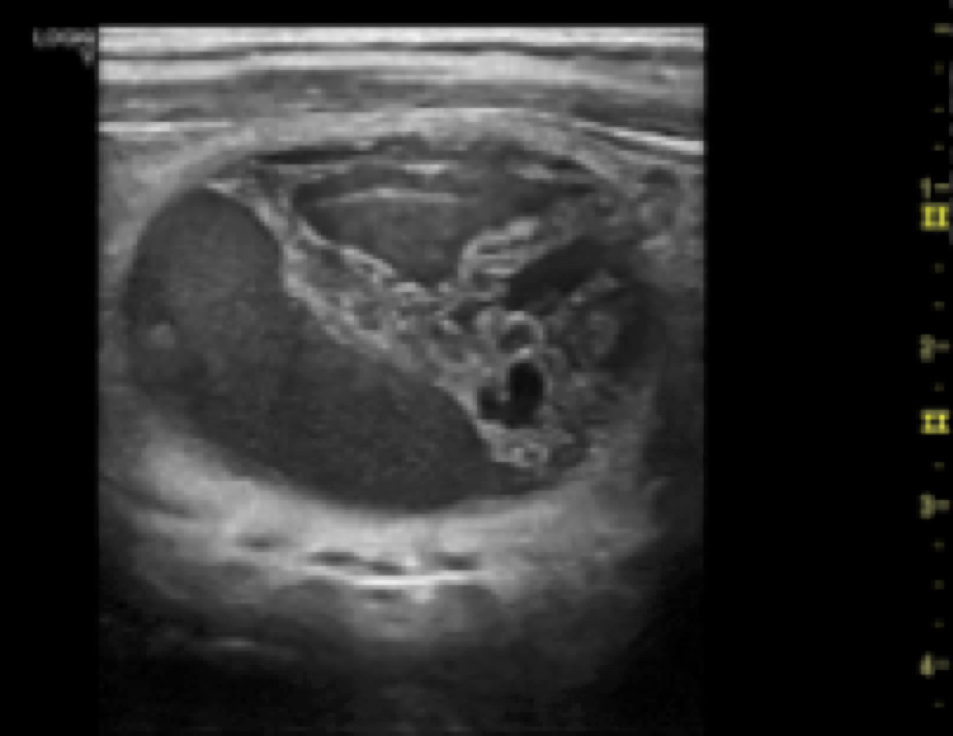

Se ha procedido a adquirir un ECÓGRAFO modelo General Electrics Logiq V2, recientemente salido al mercado, equipado con una sonda lineal de 12MHz y otra sonda convexa de 4MHz con el fin de ofrecer su uso tanto a los pacientes que lo precisen para la realización de técnicas invasivas en consulta como a los pacientes que precisen su uso en el quirófano:

Ecógrafo multidisciplinar compacto digital que puede incorporar transductores convexos, lineales y sectoriales. Tecnología General Electric de alto nivel en un equipo de tan solo 6 Kg. (Incluyendo Bateria). y reducidas dimensiones Flexibilidad, movilidad y altas prestaciones. Con capacidad de trabajar con sondas de hasta 13 MHz de formatos lineal, convex, microconvex y sectorial.

Sonda lineal de 5.0 –13.0 Mhz y 192 elementos de uso para aplicaciones músculo- esqueléticas y con capacidad de trabajo con segundo armónico.

-SONDA CONVEX 4C – RS

Sonda Convexa, múltifrecuencia (1,4 a 4,8 MHz) y de gran ancho de banda, de utilización en aplicaciones de Ecografía General. Radio de 60mm y 55º de ángulo de visión. Disponible como opción la guía de biopsia.